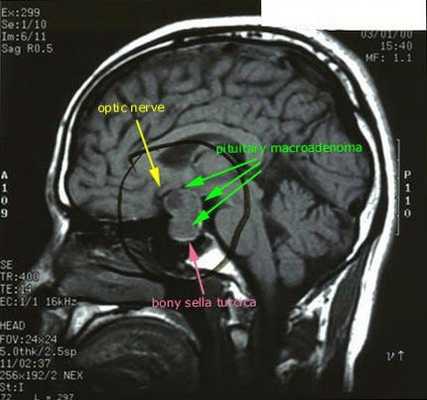

· МРТ головного мозга с контрастным усилением;

После подтверждённого гиперкортицизма необходимо проведение инструментальных методов исследования (МРТ гипофиза, КТ надпочечников).

При БИК в 80-85% случаев выявляют микроаденому гипофиза (опухоль до 10 мм), у остальных 15-20% — макроаденому (доброкачественное новообразование от 10 мм). [7]

- МРТ области турецкого седла с контрастированием;